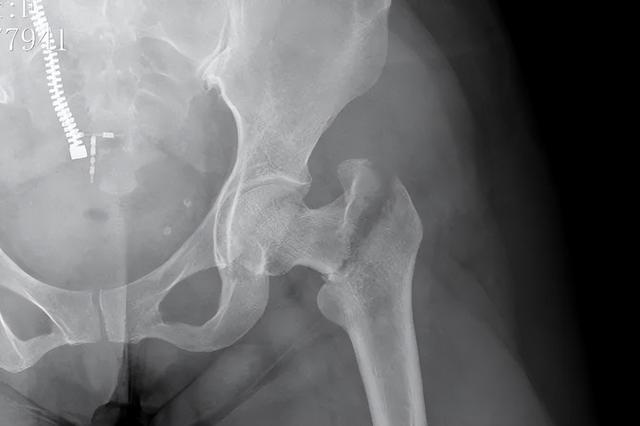

这场意外不仅让她的股骨遭遇罕见的“双段骨折”——左股骨干与转子间两处严重移位,更将骨二科团队推向了技术与勇气的双重考验。

接诊医生张程触诊时感受到明显的骨块错动,影像检查印证了最棘手的判断:患者左股骨如同被暴力折断的树枝,近端转子间与中段骨干同时出现不稳定性骨折。

这种“一骨双折”的罕见病例,具备明确手术指征。传统手术方案需在患者左大腿上下段都开刀,植入两块钢板进行固定,切口长度几乎贯穿大腿,手术风险、医疗费用与漫长康复期均令王女士望而却步。

(术前)